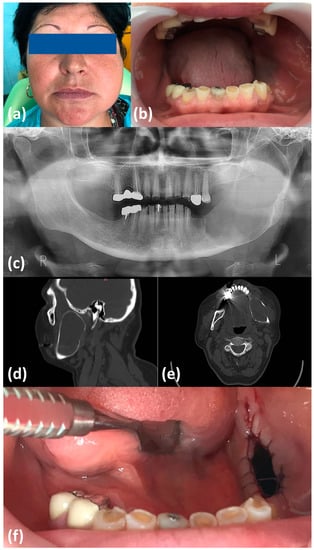

2. Case Report